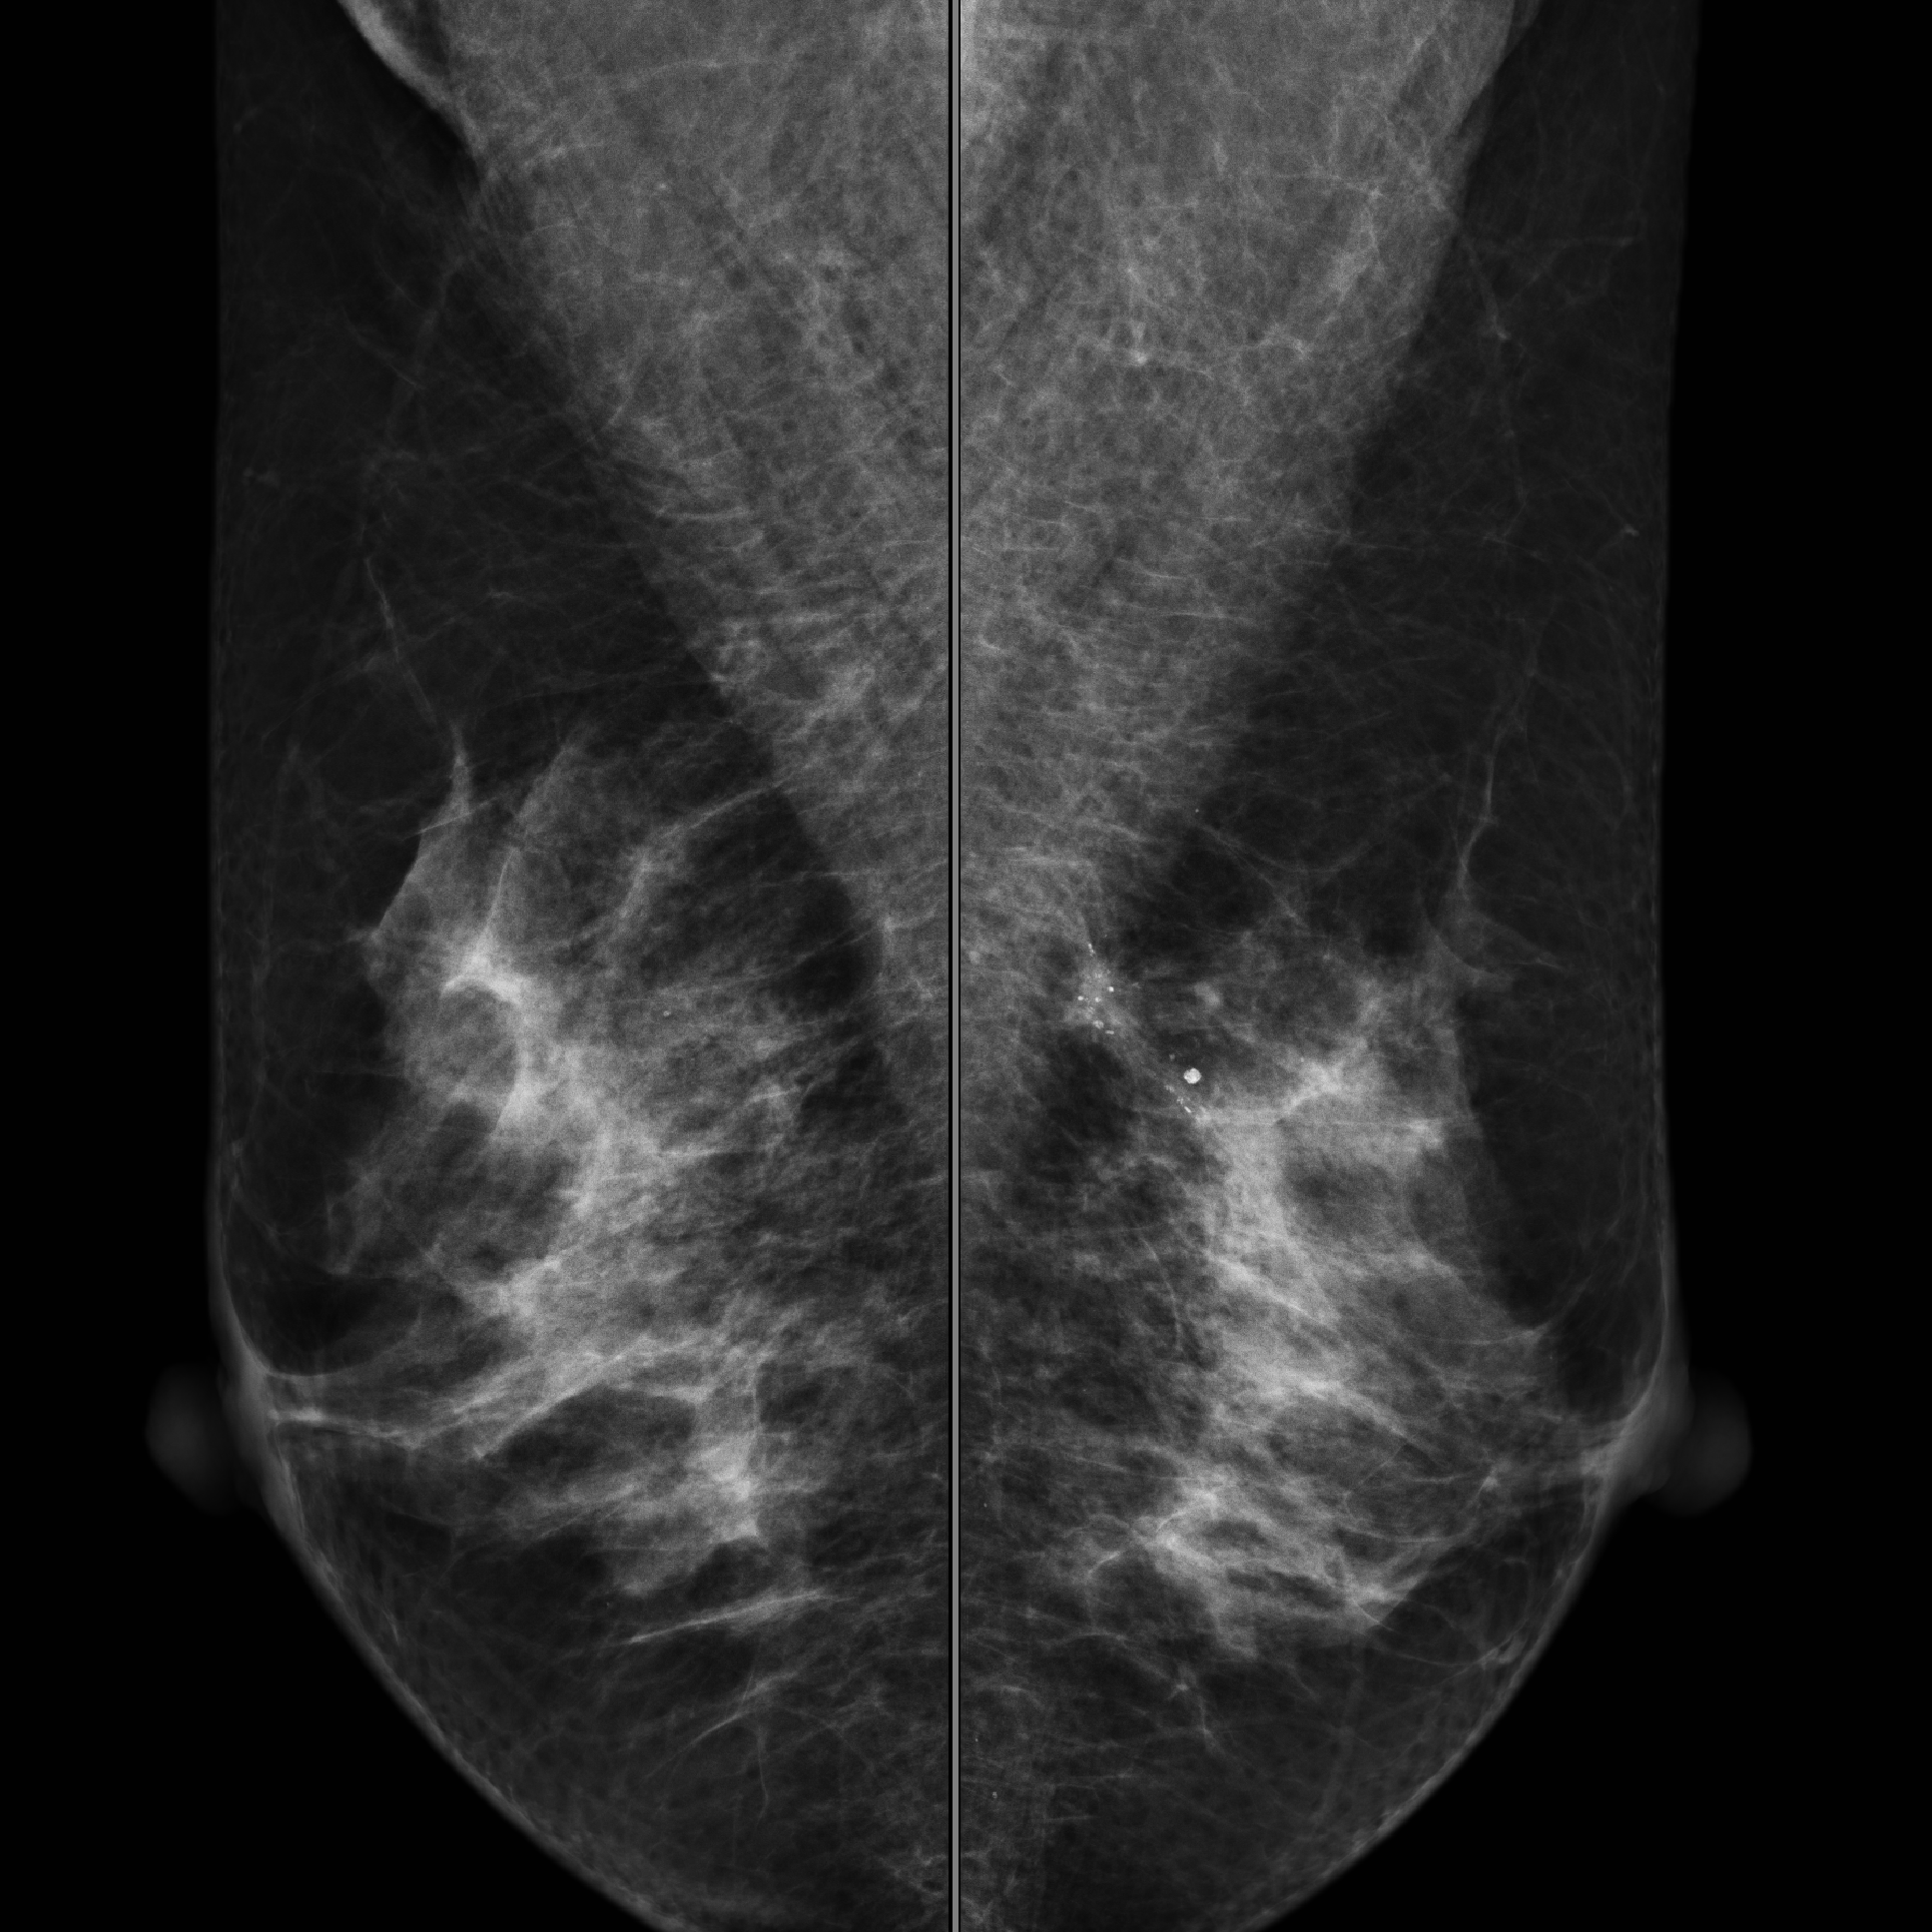

- マンモグラフィ

- 乳がん検診(マンモグラフィ)は、死亡率を減少させることが科学的に証明された検診です(メリット)

- がんは発生してから一定の大きさになるまで検査で発見することができません。マンモグラフィではがんの形状や発生する場所によっては見つけにくいため、100%見つかるわけではありません。また、がんの疑いがあると判定され精密検査を行っても、がんでないことも多くあります(デメリット)

マンモグラフィによる乳がん検診には、上記のデメリットよりも、がんで亡くなることを防ぐメリットのほうが大きいことが証明されています。